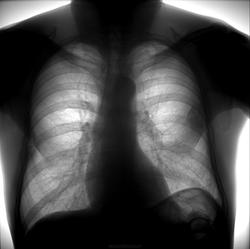

Мужчина 48 лет поступил в клинику с предварительным диагнозом левосторонняя внебольничная нижнедолевая пневмония. Жалобы на общее недомогание в течении 3-4 дней перед госпитализацией, сухой кашель, боли в грудной клетке слева. Объективно субфебриллитет, повышены острофазовые показатели.

Осумкованый паракостальный плеврит.

Не смог разобраться в легком это или в плевральной полости, возможно и плеврит. Или все-таки в легком?

Образование проецируется на шестой сегмент левого легкого

справа имеется подобная тень.только не такая четкая, так же дополнительная тень в области левой верхушки

Предлагаю в дифряд мезотелиому.

Справа костные мозоли и соответствующие изменения плевры.

Справа костные мозоли и соответствующие изменения плевры. Возможно такое же слева. Спросить о травмах.

Если диагностическая ФЛЮ, значит есть отделение и есть аппарат на 3 раб. места. Возьмите и проведите скопию, выведите, снимите, а потом описывайте. Может плеврит, может мезотелиома, может и периферический. Дополнительно анамнез, клиника и анализы.